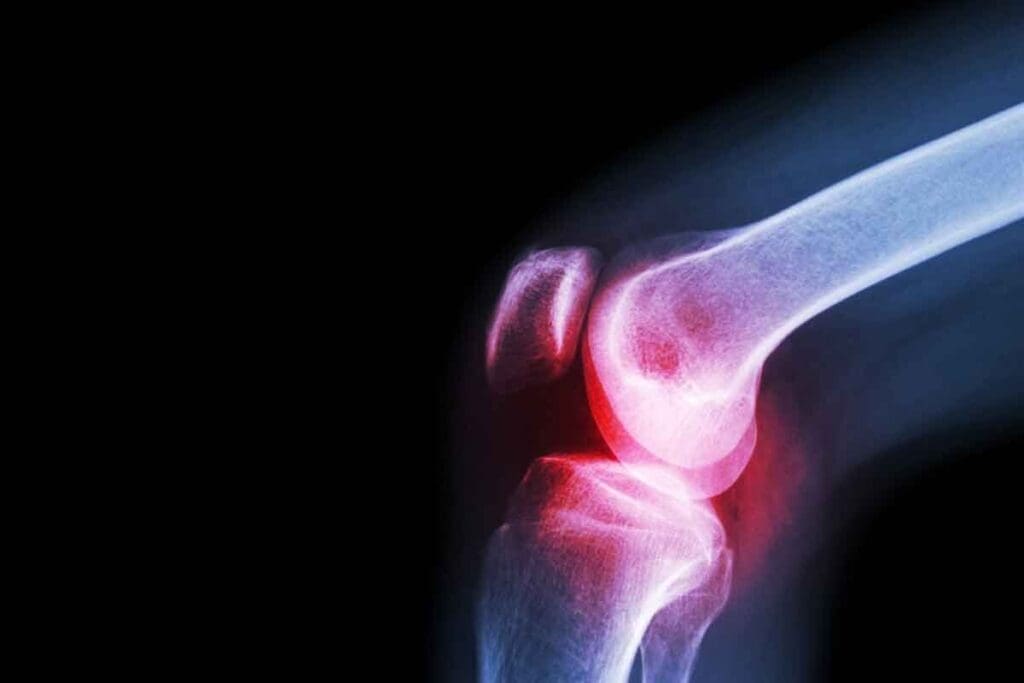

Cancer in the bone marrow can mess up blood cell production. This leads to health problems like bone pain, fatigue, and infections. It can also cause anemia.

People with bone marrow cancer often feel bone pain, get tired easily, and lose weight. Bone pain is a big issue, mainly for those with multiple myeloma. This is because the cancer breaks down bone tissue.

Imaging studies like X-rays, MRI, or PET scans check how far the disease has spread. They also look for bone damage or lesions. These studies help in staging the cancer and planning treatment.